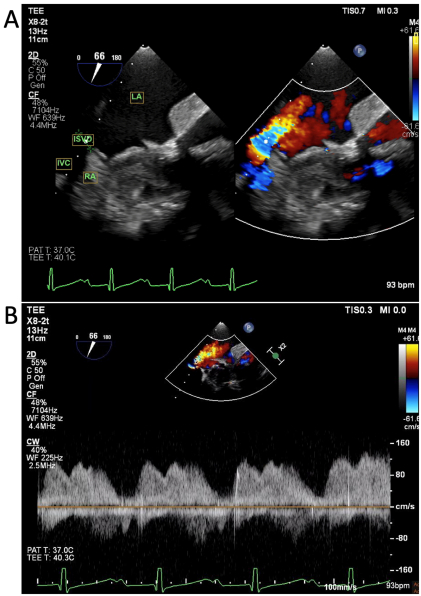

A 67-year-old woman with history of remote surgical atrial septal defect (ASD) repair in childhood and severe mitral regurgitation presented for surgical mitral valve (MV) repair. Pre-operative transesophageal echocardiography (TEE) revealed flail P2 scallop of the MV and no evidence of intracardiac shunt. She underwent redo sternotomy with chordal-sparing bioprosthetic MV replacement on cardiopulmonary bypass (CPB) via femoral cannulation. After coming off CPB, she experienced hypoxemia despite supplemental oxygen. Chest X-ray revealed no acute pulmonary pathology. Initial transthoracic echocardiogram (TTE) showed normal biventricular function, well-seated and normal position and function of the mitral bioprosthesis. TEE showed no evidence of transseptal shunting but revealed a communication between the inferior vena cava (IVC) and left atrium (LA) with continuous right to left shunting (Fig 1). CT angiography of the chest demonstrated an inferoposterior interatrial communication associated with an overriding IVC, consistent with an inferior sinus venosus defect (ISVD) (Fig 2a).

Given patient preference to avoid redo sternotomy, she underwent percutaneous transcatheter closure of the defect using a 12 mm Amplatzer vascular plug (AVP II) with immediate resolution of the hypoxemia following implantation (Fig 3). She returned to her functional baseline with preserved exercise tolerance on follow up with no recurrence of hypoxemia.